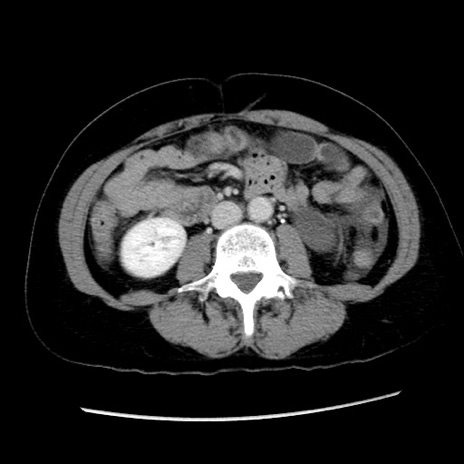

症例10(横断像)

【症例】 50歳代女性

【主訴】 腹痛

【現病歴】前日生レバーを食べた。今朝に排便あり。 昼前に突然発症の腹痛を生じ、当院救急外来を受診した。

【既往歴】 子宮筋腫にてで子宮全摘後

【身体所見】 意識清明、腹部:平坦、軟、下腹部やや左を中心に圧痛・反跳痛あり、筋性防御あり

【データ】WBC 7800、CRP 0.07